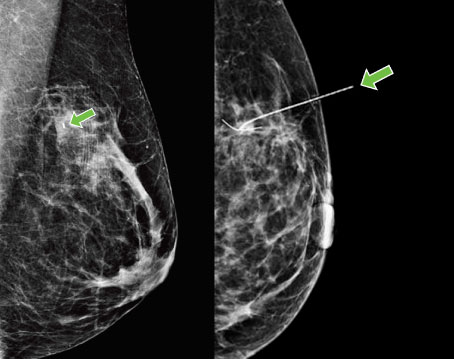

a breast with a green arrow pointing to the left sideTiny breast tumours are difficult for surgeons to find and remove during surgery. For years, the only way to do it was to insert a wire (known as a harpoon) into the breast to mark the tumour during pre-surgical imaging. But the wire was uncomfortable and sometimes shifted.

Today, a tiny radioactive seed is implanted instead, making it easier for surgeons to find and fully remove the cancer.